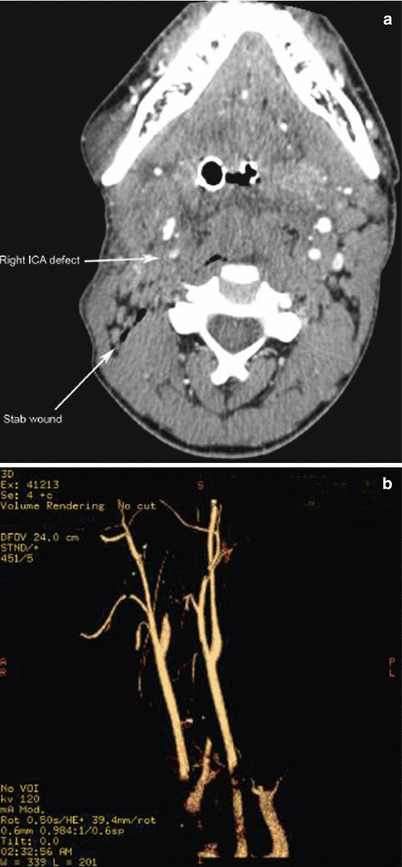

Fig. 16.8

(a) Stab wound to the right neck with evidence of internal carotid artery (ICA) injury. Patient with large middle cerebral artery (MCA) territory thrombotic stroke successfully treated with neurointerventional extraction of thrombus and coiling of the right proximal and distal ICA with excellent functional recovery. (b) CTA reconstruction of the right ICA injury demonstrating abrupt cutoff of the right ICA without distal reconstitution

Another study prospectively examined the usefulness of CT angiography as the initial screening mechanism in stable patients with neck injuries penetrating the platysma. Inaba et al. demonstrated a sensitivity of 100 % and specificity of 93.5 % for the detection of vascular and aerodigestive tract injuries. The use of CT angiography has been shown to decrease the rate of formal surgical neck exploration, as well as the rate of negative neck exploration when used in stable patients not requiring emergent exploration.